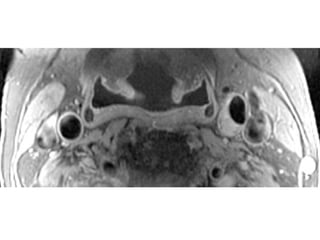

The document describes the Pathway MRITM Carotid Array coil, which is designed for high resolution imaging of small soft tissue structures like the carotid arteries. It provides images showing atherosclerotic plaque buildup in the carotid arteries, including plaque in the common carotid artery, carotid bifurcation, and internal carotid artery stenosis and plaque.